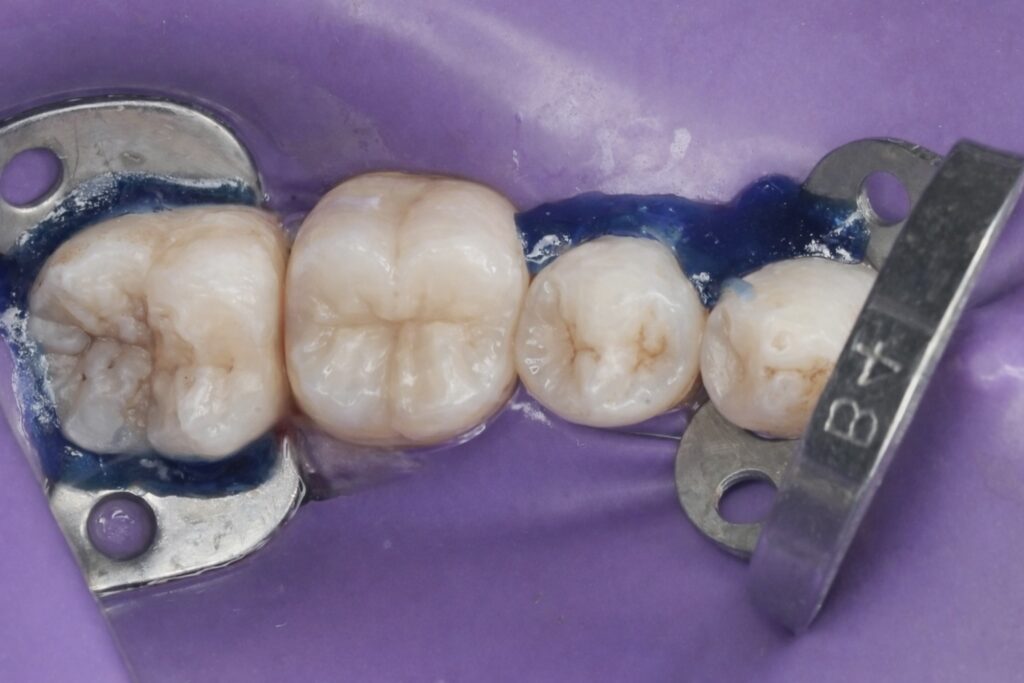

8. Occlusal Anatomy Reconstruction

Using layered composite technique:

- Dentin layer for opacity

- Enamel layer for translucency

- Cusp-by-cusp buildup

- Precise occlusal morphology reproduction

Anatomical reproduction improves stress distribution and functional longevity.

9. Finishing and Polishing

- Fine diamond refinement

- Multi-step polishing system

- Verification of proximal contact

- Occlusal adjustment

Proper finishing reduces plaque retention and enhances marginal integrity.